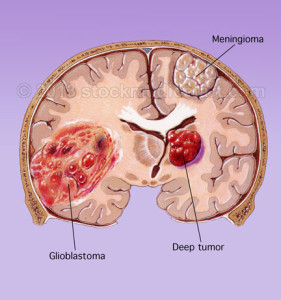

Il glioblastoma può provenire da una serie di cellule del sistema nervoso

A lungo i ricercatori hanno creduto che il glioblastoma multiforme (GBM), il tipo più aggressivo di tumore cerebrale primario, inizia…